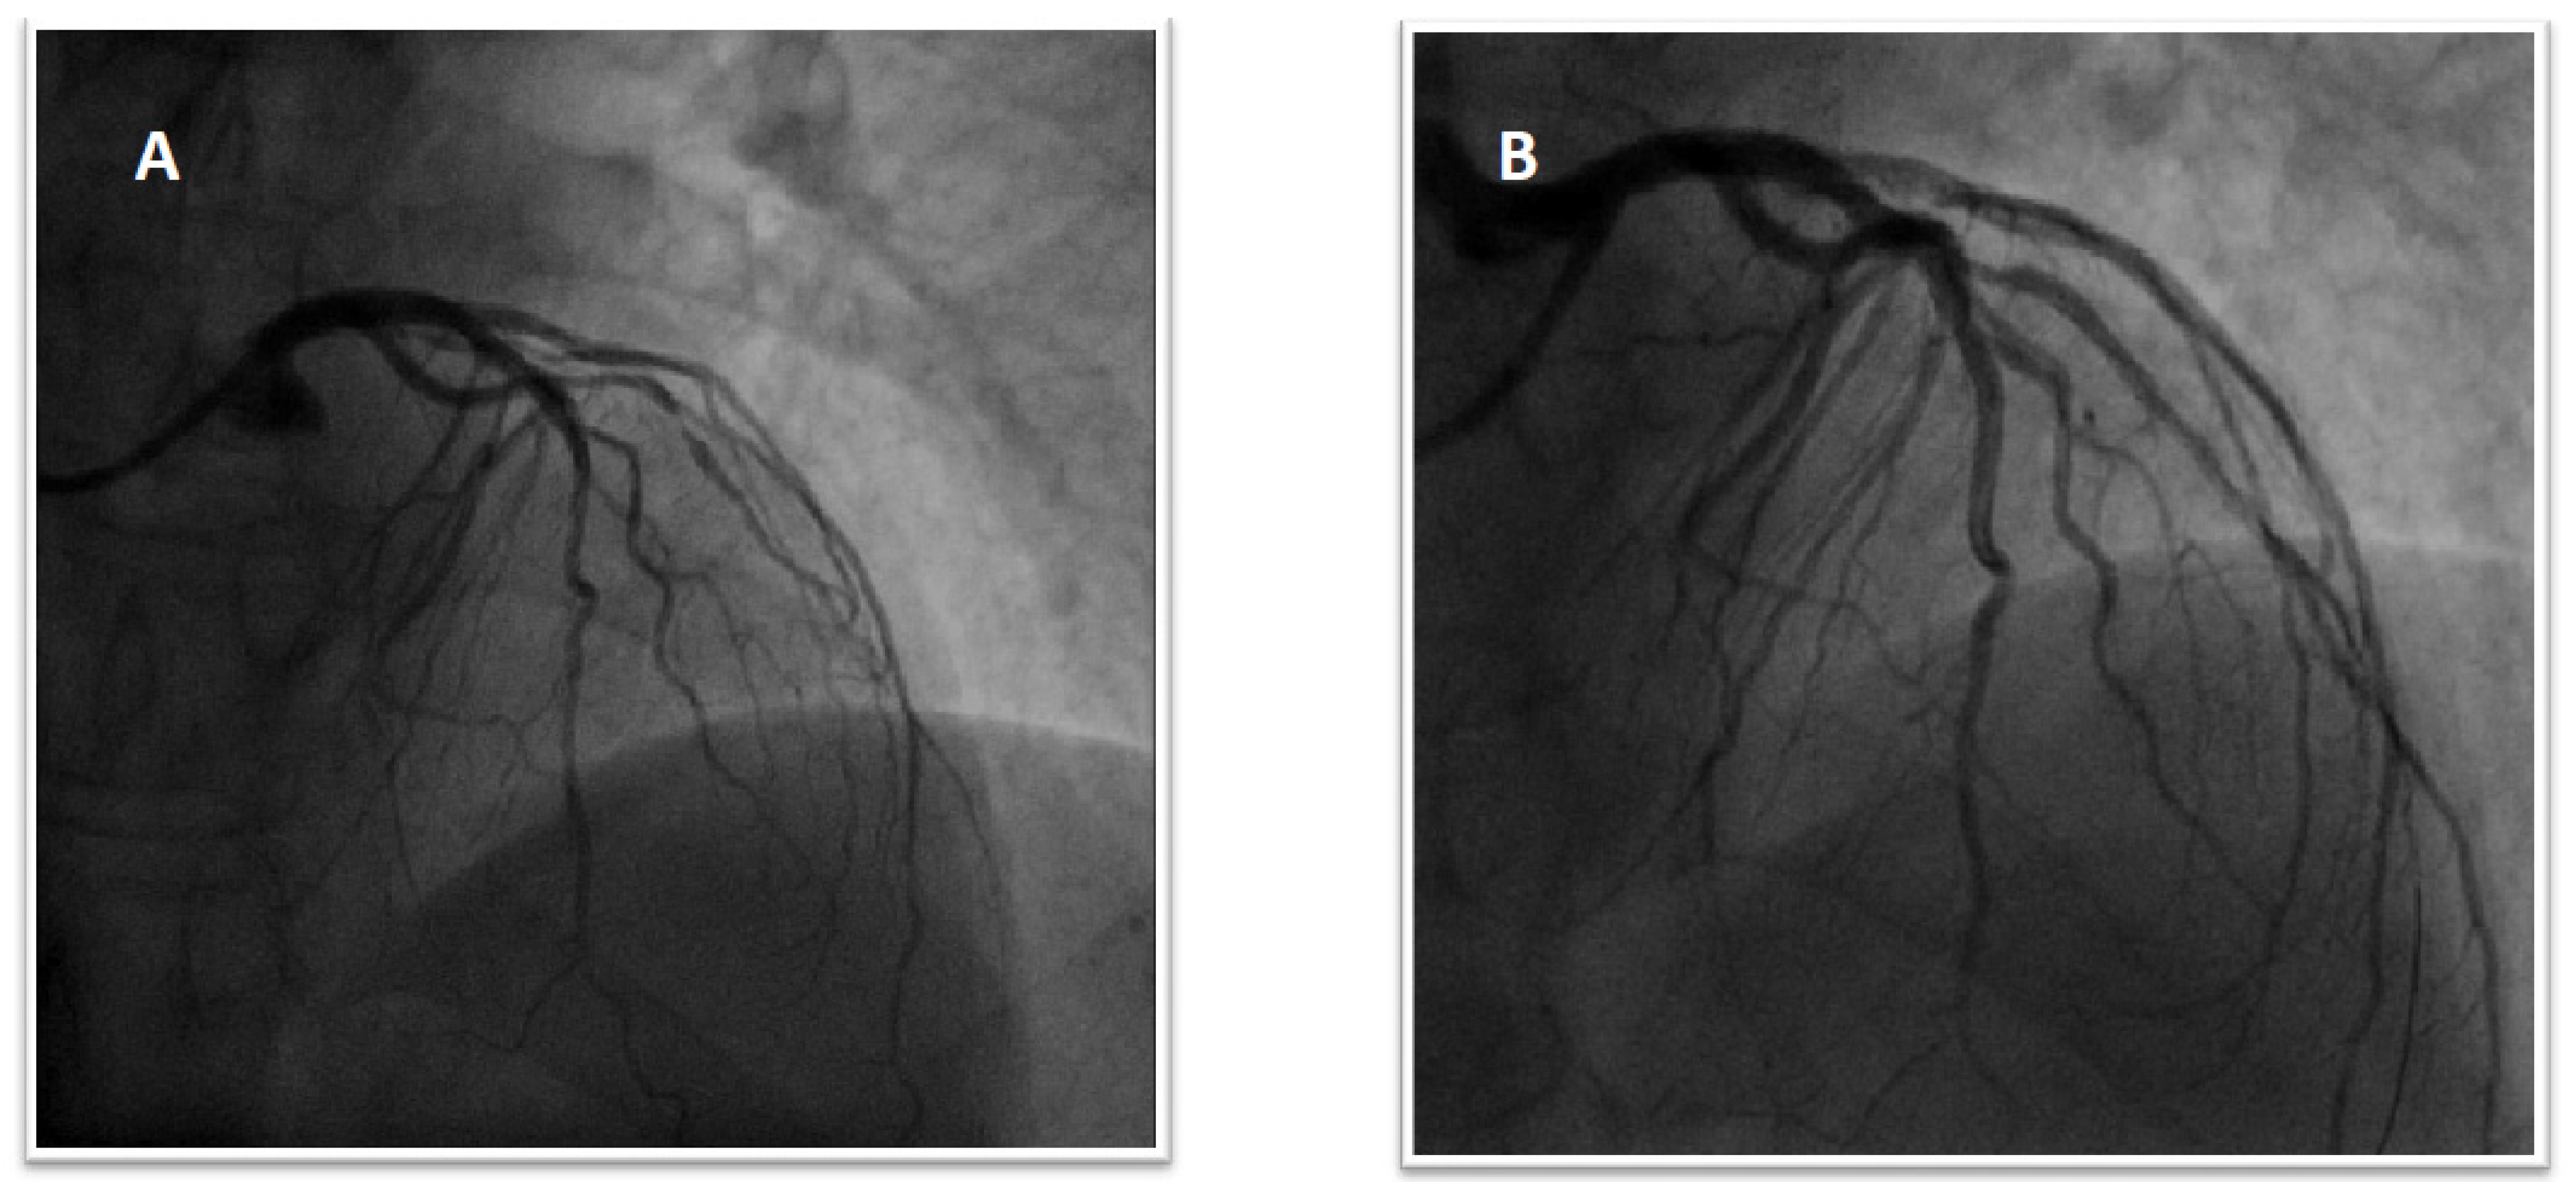

Figure 5.

Coronary angiogram revealing the patency of previously implanted stents.